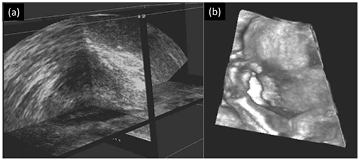

Visualizing the acquired volumes is a key point in 3DUS. The most frequently used visualization techniques are multi-planar reformatting (MPR) and surface rendering. In MPR, it is possible to browse through the volumes selecting e.g. a couple of intersecting cross planes (Nelson et al 1996) (figure 3(a)). Surface rendering is based on ray-casting techniques. It is used when a high contrast is present between different tissues, allowing surface reconstruction of e.g. foetal images (Lee 2003) (figure 3(b)) or cardiac images (Deng and Rodeck 2006). Also volumetric rendering (VR) was introduced using techniques such as maximum intensity projection (Bamber et al 1992).

Figure 3. (a) Example of MPR view of a prostate, showing intersecting extracted planes. (b) Example of 3DUS surface render of the face of a foetus. (Images reproduced with kind permission of Fenster et al (2002)).